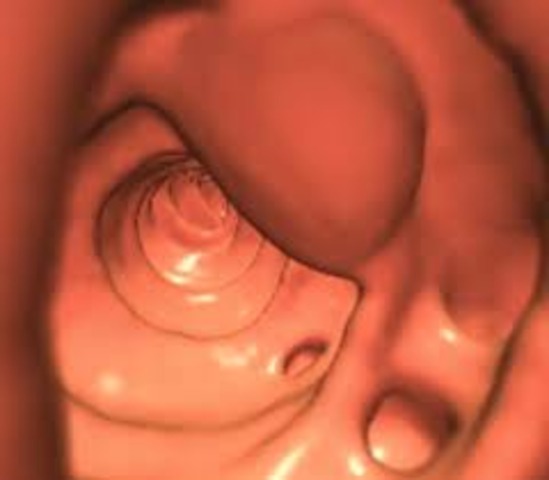

• Colonoscopy and Flexible Sigmoidoscopy

Colonoscopy and Flexible Sigmoidoscopy

Beginning at the age of 50, men and women need a colonoscopy and a flexible sigmoidoscopy. During these tests, a doctor will insert a long flexible tube into the rectum to view the inner lining of the rectum and the colon. A flexible sigmoidoscopy only goes 1/3 of the colong, but the colonoscopy shows the entire colon. These tests test for colorectal and colon cancer. Colonoscopy is done every 10 years and the flexible sigmoidoscopy is done every 5 years.